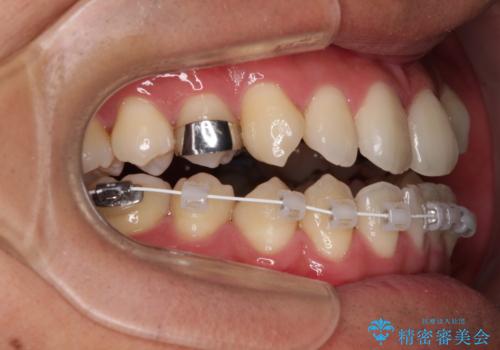

上顎の急速拡大装置を使用して、上顎骨を側方に拡大することで上顎歯列弓を拡大し、それに伴い下顎歯列弓も拡大できるようにして、歯列を整えていくこととしました。